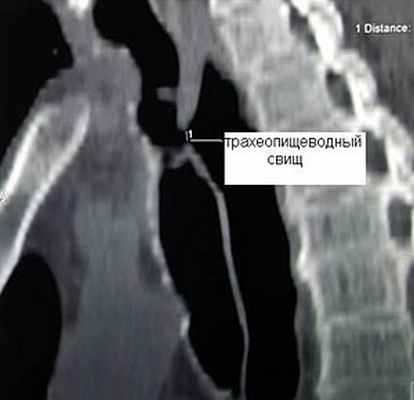

Клиническая диагностика трахеопищеводных свищей, как правило, не вызывает трудностей. Проявляются они приступообразным кашлем, который возникает во время приема пищи. Однако уточнение их локализации при рентгенологическом исследовании с барием и эзофагоскопии вызывает существенные трудности, особенно при небольших размерах свища. Более информативным оказывается трахеоскопия, при которой удается определить размеры свища, расстояние от голосовых связок и карины. Кроме того, значительную помощь в выявлении трахеопищеводных свищей оказывает также компьютерная томография.

![]() Рис.9. Компьютерная томограмма больного с трахеопищеводным свищом. | ![]() Рис. 10. Трахеоскопия больного с трахеопищеводным свищом, осложненным стенозом трахеи. |